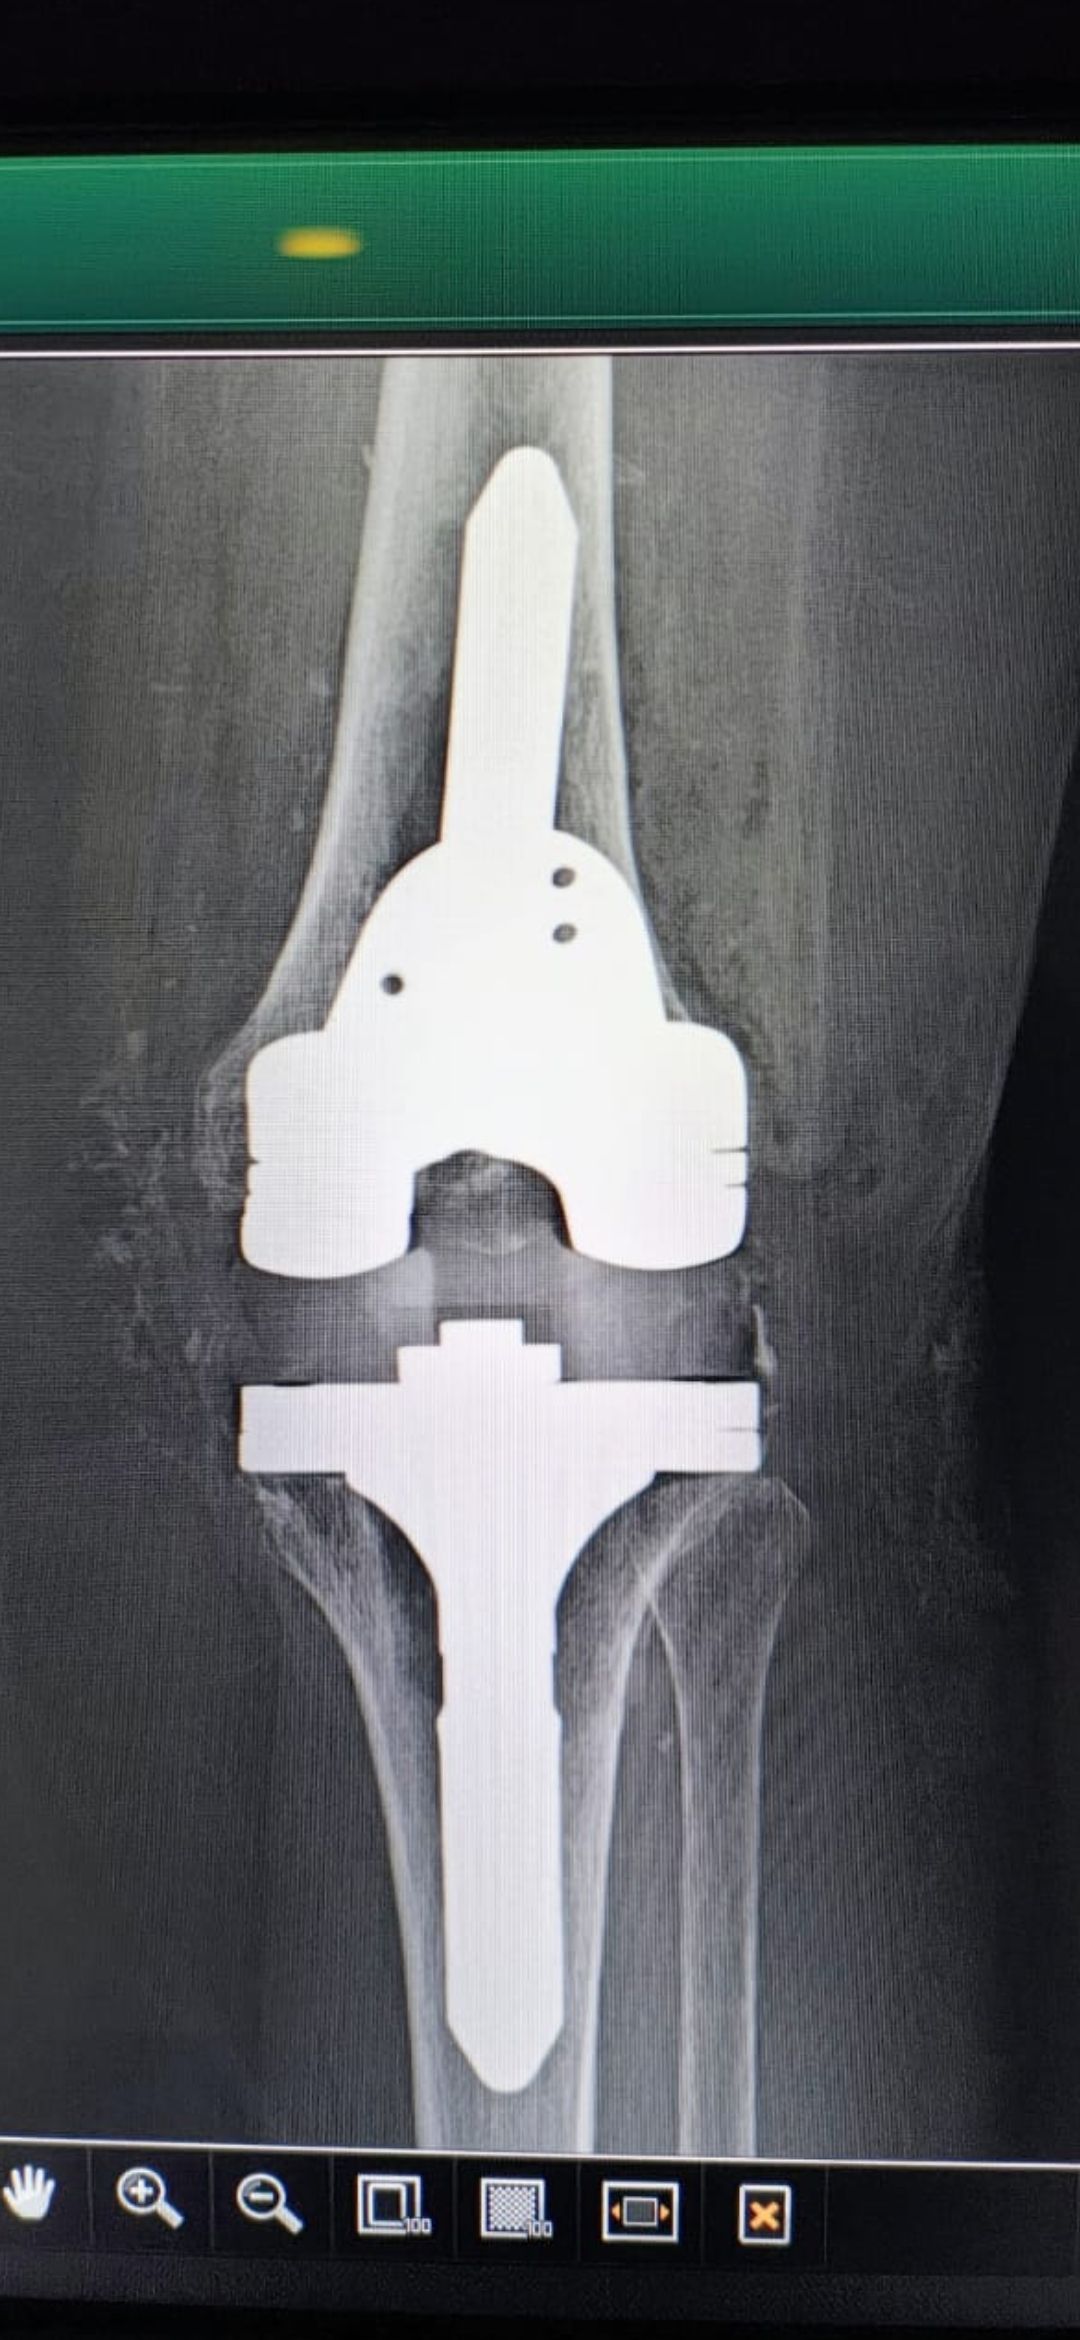

Soy   egresado  de  la  Universidad Autonoma de   Nuevo  Leon. especialidad de ortopedia y traumatologia  en    hospital  numero  21  del  IMSS ne Monterrey  N.L ,con entrenamiento en la  subespecialidad  de   reconstrucion  articular  y  artroscopia  que incluye  lesiones  de  meniscos  , reconstruccion de ligamentos cruzados , lesiones  condrales ,  gonartrosis   tengo  una  historia laboral    institucional de 30  años    hasta el 30  de lulio del 2024 estuve  10  años  en  el  modulo  de  artroscopia  con aproximadamente   1120    artroscopias  de rodilla   y  15 años  en  el  departamento  de    artroplastia  de rodilla  o  de  reemplazos  articulares   ,  los  ultimos   15  años    como profesor  adjunto   y titular  en los cursos    de pre  y posgrados  de  traumatologos  en la  subespecialidad  de  con aproximadamente   160 cirugias  institucionales    en   artroplastia de  rodilla    por  cada año   y  un  numero menor en el  medio particular  dando un total  aproximado  de  2,560  cirugias . de  estas  el  10%    de  revision  y  5%  preotesis    tumorales    de  actualmente   en  funciones  en  el  medio privado  y  acreditado  en todos los  hospitales  de la  localidad  y  con todas  las  aseguradoras   de  gastos  medicos .